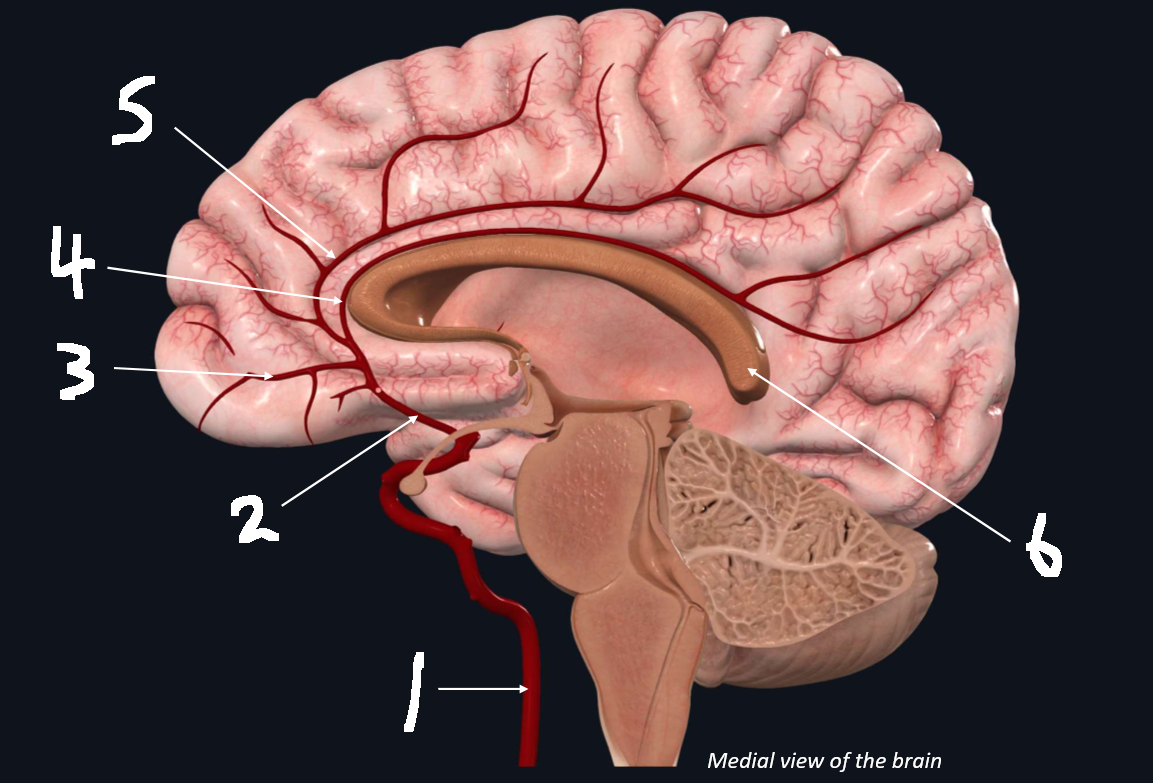

What is 1?

internal carotid artery

What is 2?

anterior cerebral artery

What is 3?

frontopolar artery

What is 4?

pericallosal artery

What is 5?

callosomarginal artery

What is 6?

corpus callosum